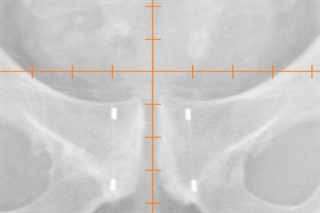

Fleximarc G/T Markers, 1 x 3 mm markers, 10 mm spaced, 18 GA ETW x 20 cm needle

The FlexiMarc G/T Marker provides distinctive non-biological projection with easily definable nodes. The gold nodes are connected with a fine titanium line, which creates the optimal performance characteristics and visulaization. Sterile Placement Needle (18GA ETW x 20cm) with (1 x 3mm)-10mm Spaced FlexiMarc G/T Marker, pouch of 1 pre-spaced (2 markers).